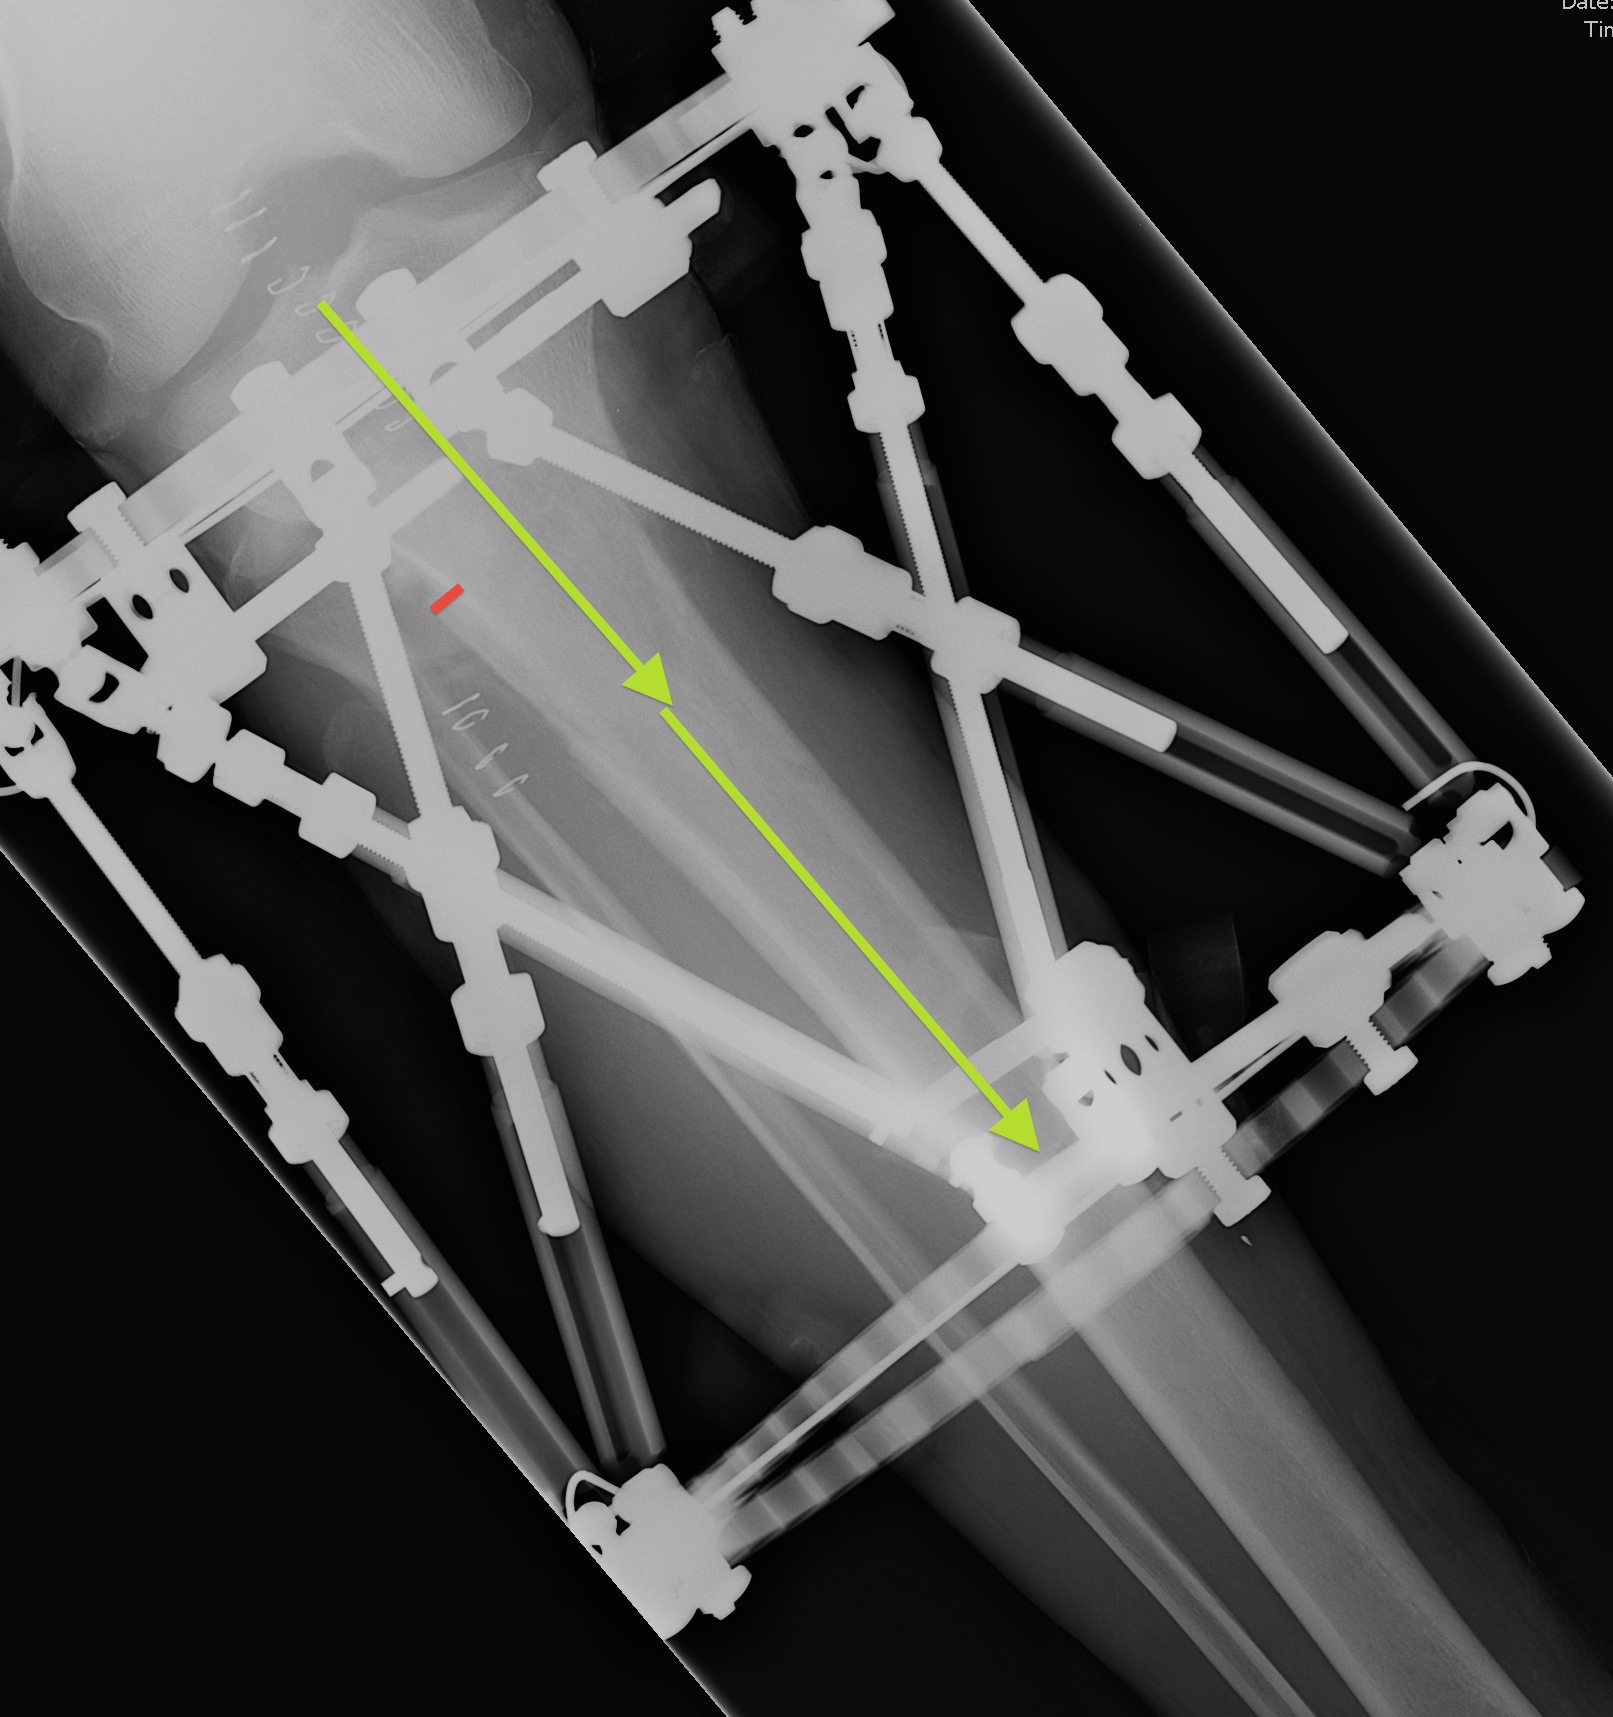

Measure AP and Lateral View Axial Frame Offset

The tibia is not in the centre of the rings

- usually anterior

- need to tell computer where the proximal fragment is in reference to the rings